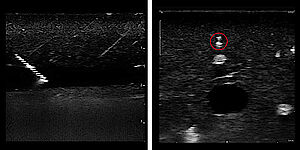

Mesmo em ângulos de punção muito grandes, a agulha apresenta uma excelente visibilidade.

• Excelente ecogenicidade devido ao marcador de ultra-som Rhombus Cut

Convença-se da visibilidade do REGANESTH® unoplex: